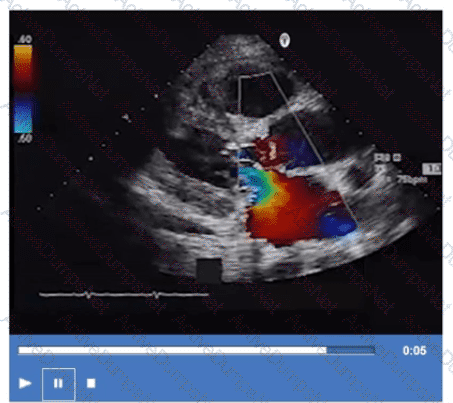

What is the direction of the mitral regurgitant jet in this video clip?

Which next step is appropriate after obtaining the Doppler signal in this image?